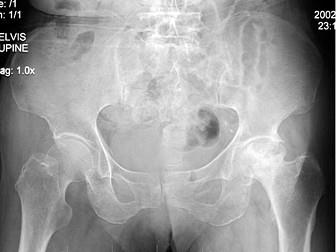

问题 38岁男性患者,因左髋关节疼痛跛行1年半,经治疗症状无明显好转,双髋关节正位片摄片如图所示,最佳诊断是 ( )

选项 A、左股骨头坏死(稳定期) B、左髋关节肿瘤 C、左股骨头坏死(早期) D、左股骨头坏死(活动期) E、左髋关节结核

答案 D